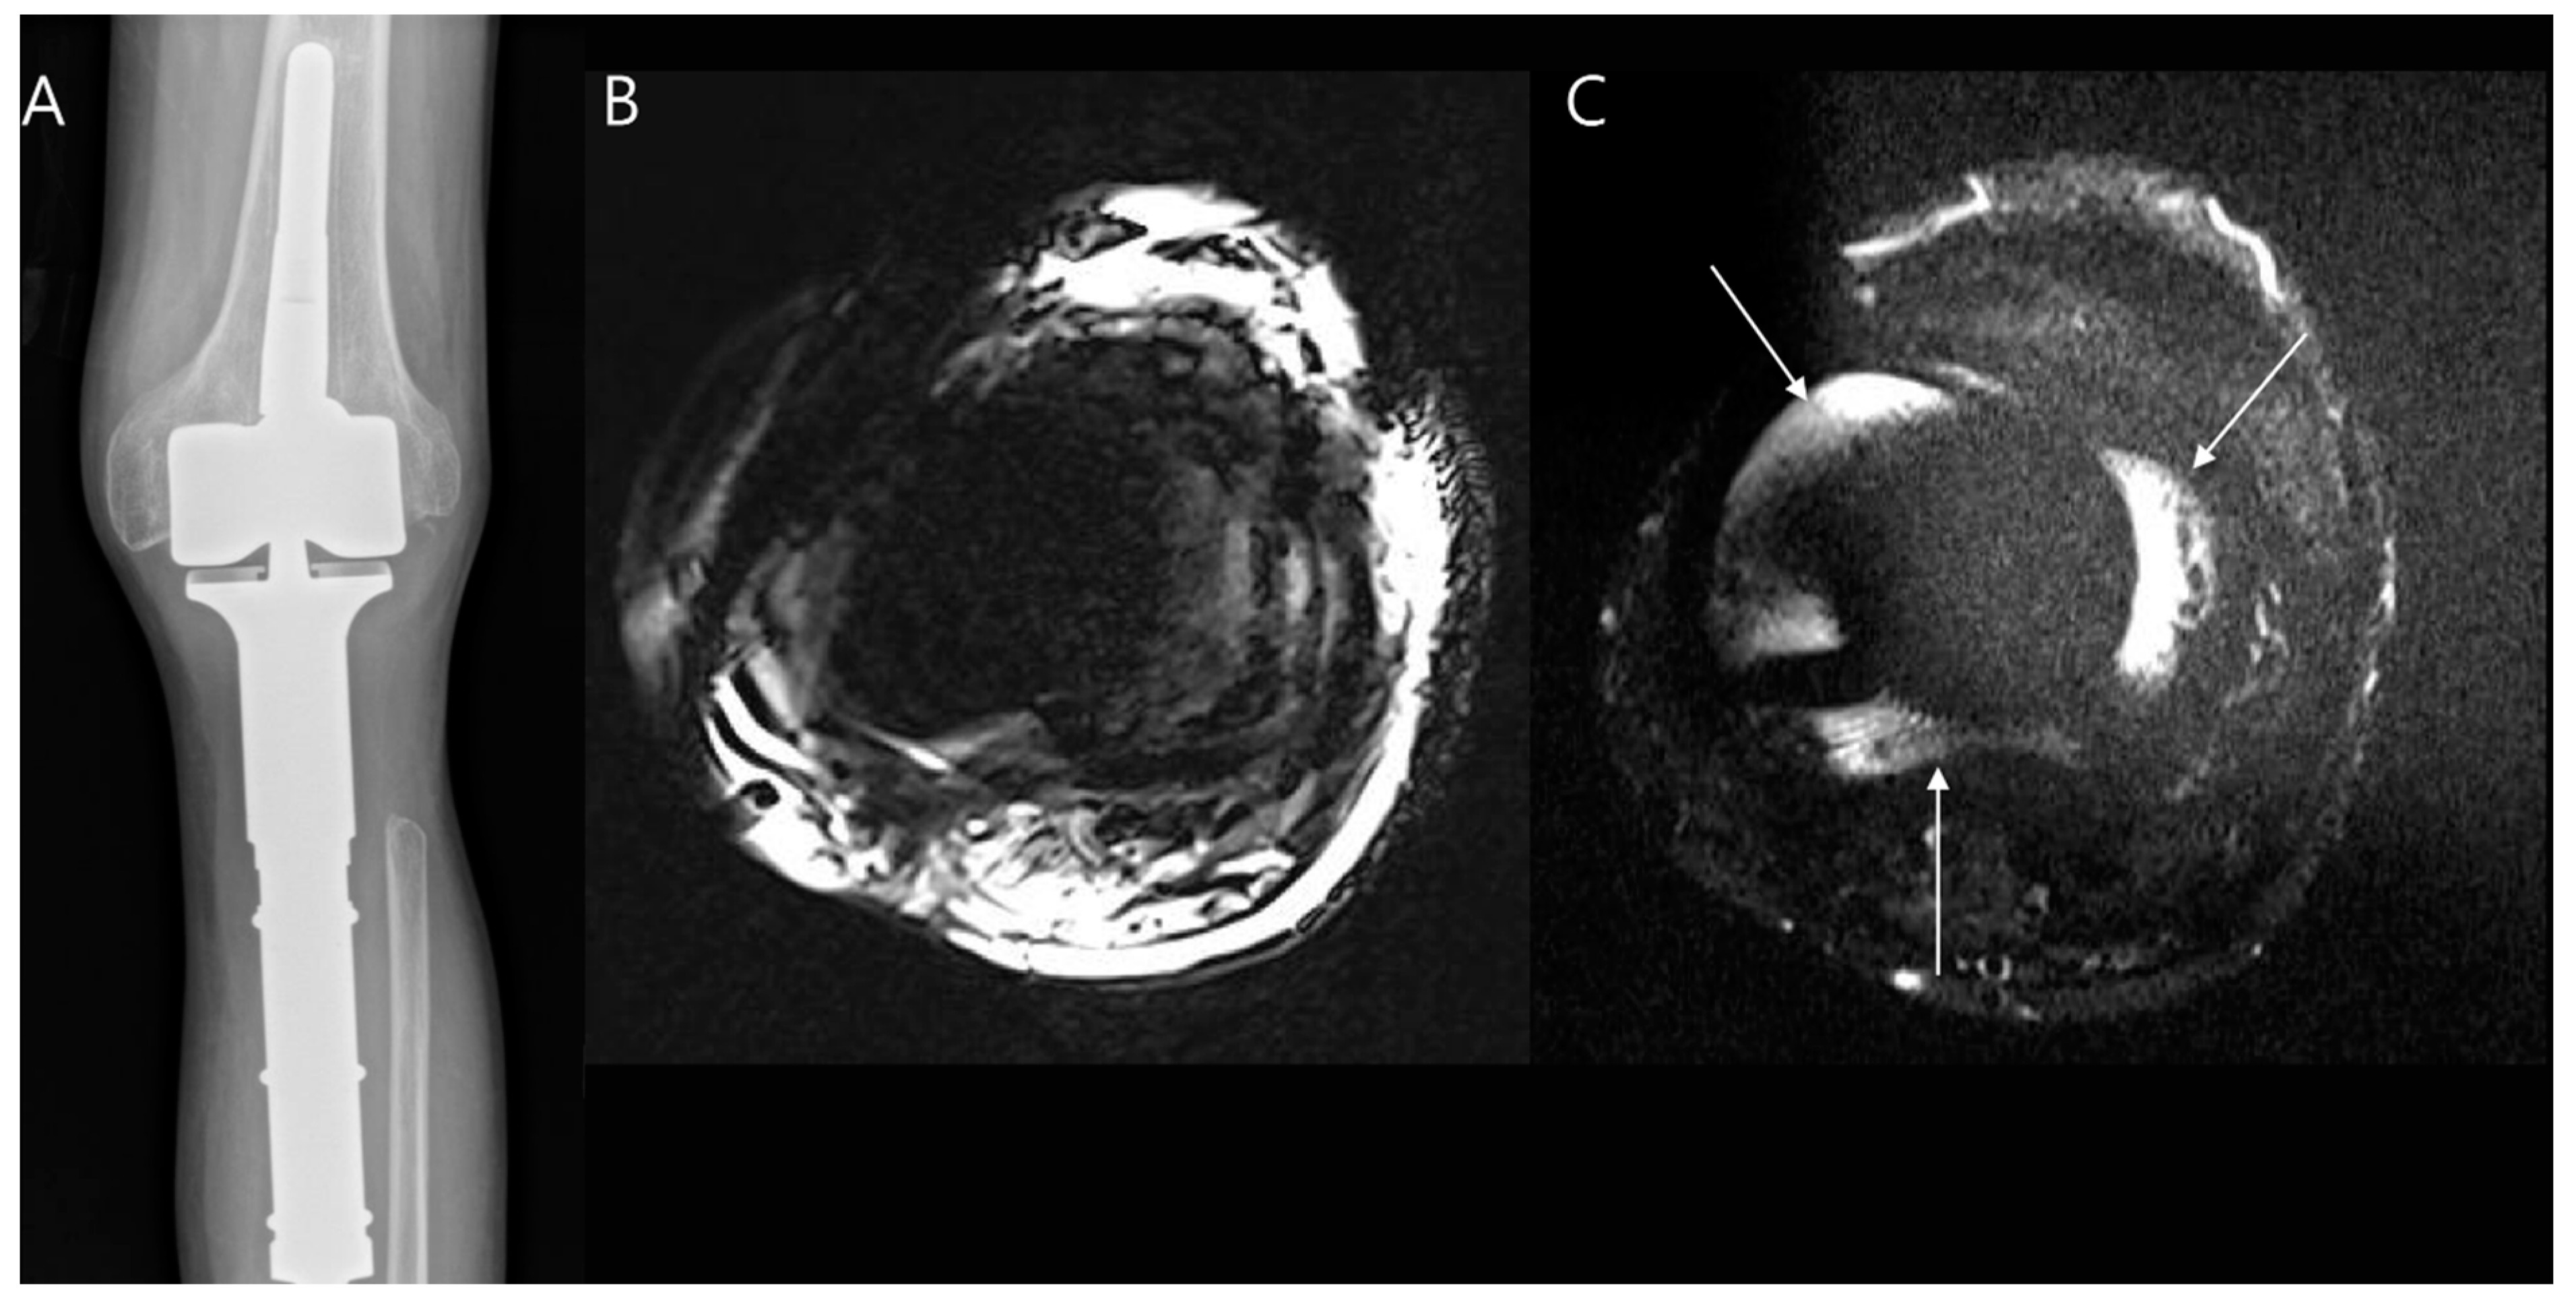

- Jungmann, P.M.; Ganter, C.; Schaeffeler, C.J.; Bauer, J.S.; Baum, T.; Meier, R.; Nittka, M.; Pohlig, F.; Rechl, H.; von Eisenhart-Rothe, R.; et al. View-Angle Tilting and Slice-Encoding Metal Artifact Correction for Artifact Reduction in MRI: Experimental Sequence Optimization for Orthopaedic Tumor Endoprostheses and Clinical Application. PLoS ONE 2015, 10, e0124922. [Google Scholar] [CrossRef] [PubMed]

- Busch, A.; Jäger, M.; Beck, S.; Wegner, A.; Portegys, E.; Wassenaar, D.; Theysohn, J.; Haubold, J. Metal Artefact Reduction Sequences (MARS) in Magnetic Resonance Imaging (MRI) after Total Hip Arthroplasty (THA): A non-invasive approach for preoperative differentiation between periprosthetic joint infection (PJI) and aseptic complications? BMC Musculoskelet. Disord. 2022, 23, 620. [Google Scholar] [CrossRef]

- Schwaiger, B.J.; Gassert, F.T.; Suren, C.; Gersing, A.S.; Haller, B.; Pfeiffer, D.; Dangelmaier-Dawirs, J.; Roski, F.; von Eisenhart-Rothe, R.; Prodinger, P.M.; et al. Diagnostic accuracy of MRI with metal artifact reduction for the detection of periprosthetic joint infection and aseptic loosening of total hip arthroplasty. Eur. J. Radiol. 2020, 131, 109253. [Google Scholar] [CrossRef]

- Feuerriegel, G.C.; Sutter, R. Managing hardware-related metal artifacts in MRI: Current and evolving techniques. Skelet. Radiol. 2024, 53, 1737–1750. [Google Scholar] [CrossRef]